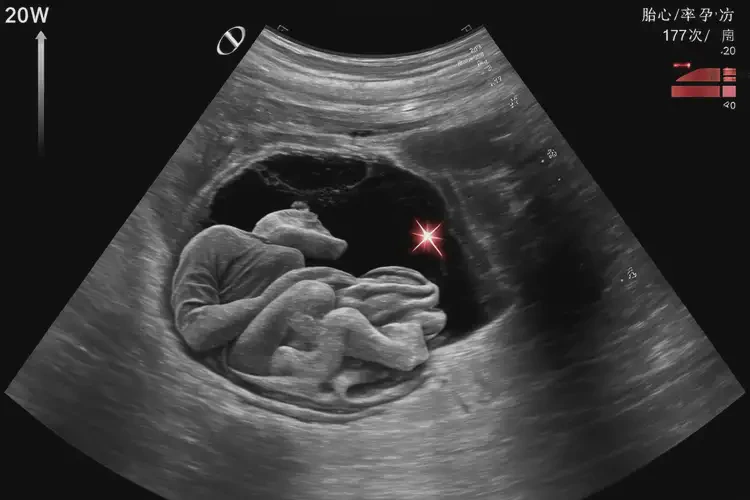

孕20周1天胎心率177還要保胎嗎

胎心率177次/分鐘在孕20周1天時(shí)屬于正常范圍,通常無需特殊保胎措施。

胎心率是指胎兒心臟每分鐘跳動(dòng)的次數(shù),是評(píng)估胎兒健康狀況的重要指標(biāo)之一。在孕20周左右,胎兒的胎心率通常在120-180次/分鐘之間波動(dòng)。胎心率為177次/分鐘雖然接近上限,但仍在正常范圍內(nèi)。

孕20周1天胎心率177還要保胎嗎(圖1)